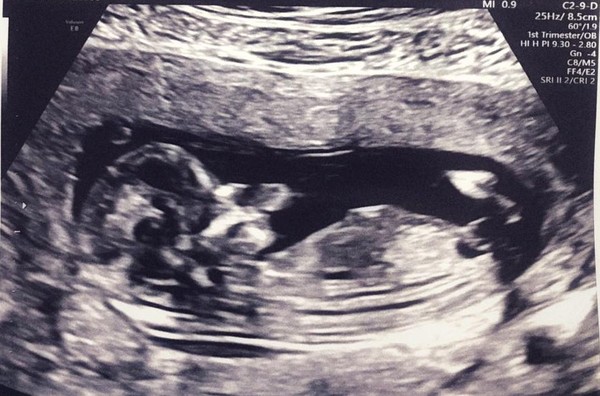

Pip231018 · 01/10/2019 18:51

I've just got back from my dating scan, it wasn't the greatest of experiences. The baby wasn't in the right place and it took 40 minutes of jabbing/poking and pressing. The Sonographer wasn't overly empathetic and quite matter of fact. Every question I asked like 'what's my due date?' She said she didn't know/couldn't remember. I asked if she managed to get the measurements for the fluid behind the babies neck and she said she couldn't confirm. When I asked if I could be rescanned if she couldn't get the measurements, she said no.

The second half of the appointment was much more positive and the midwives and Drs were lovely. They did confirm the measurements for me as the Sonographer was able to provide it. I am only measuring 11+4 and I wish I'd have gone a week later - just really want to get through this first 13 weeks. My midwife said if I was really worried about MC etc then 16 weeks is the week I'm aiming for to feel like I'm in the clear. My scan isn't that great, but have attached it in case anyone wants to see. X

April 2020 Babies - Thread 2!

@Catconfusion they told me my 20 week scan date already and I'm just hoping it's not the same Sonographer. If the midwife hadn't been so informative/I didn't get given the measurements then I definitely would have made a complaint and asked for another scan.